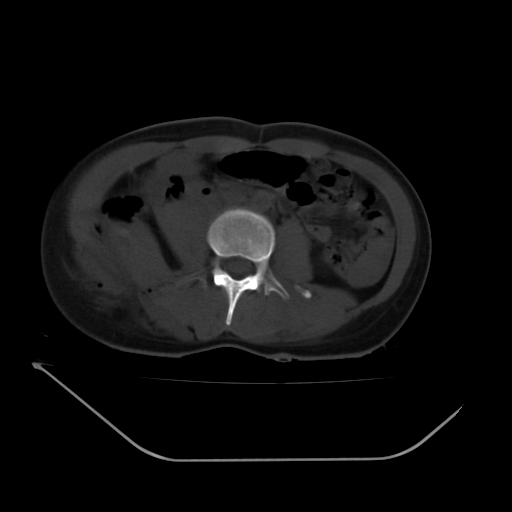

以下是引用liuyue在2008-7-19 13:02:00的发言:[br]1.肝右叶后下段及右肾挫裂伤伴腹腔积血。[br]2.右侧多发性肋骨骨折、横突骨折、右髂骨骨折伴周围软组织挫伤。[br]3.右侧腰大肌肿胀,并可见低密度影,如为气体,则肠道挫裂伤待除外。

以下是引用zhengfaming在2008-7-19 14:42:00的发言:[br]1.肝右叶后下段及右肾挫裂伤伴腹腔积血。脾脏挫裂伤待排[br]2.右侧多发性肋骨骨折、横突骨折、右髂骨骨折伴周围软组织挫伤。[br]3.右侧腰大肌肿胀,并可见低密度影,如为气体,则肠道挫裂伤待除外

以下是引用道哥在2008-7-19 16:52:00的发言:[br]肝右叶后下段及右肾挫裂伤、脾破裂伴腹腔积血。[br]2.双侧多发性肋骨骨折、横突骨折、右髂骨骨折伴周围软组织挫伤。[br]3.右侧腰大肌肿胀,并可见低密度影,如为气体,则肠道挫裂伤待除外。